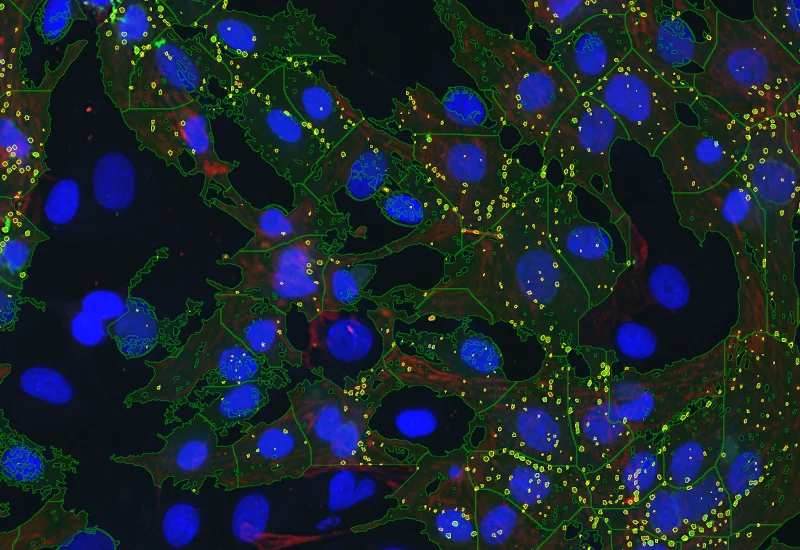

Original Image

Dot detection